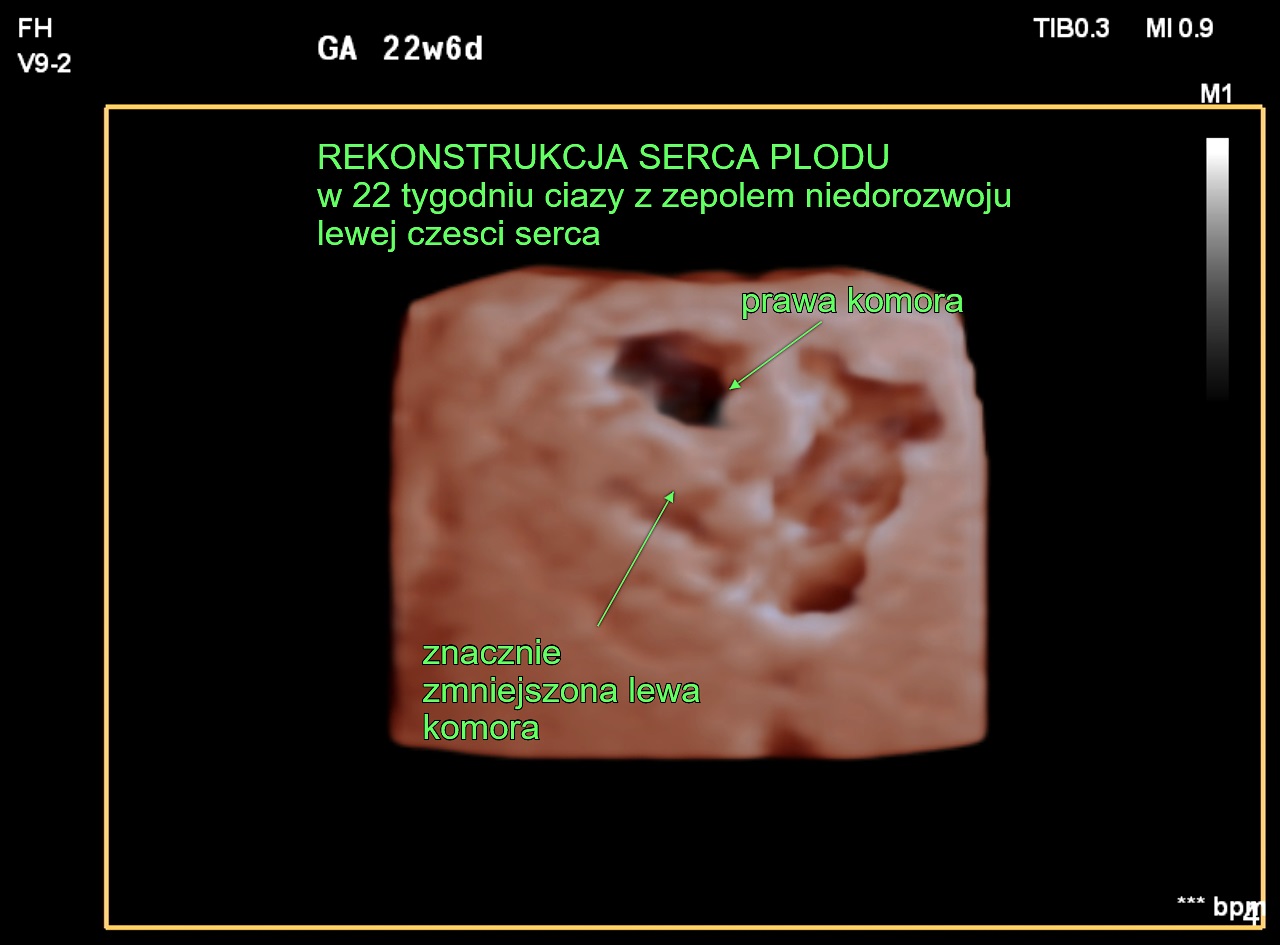

W 2011 r. kardiolodzy zajmujący się diagnostyką prenatalną w zespole prof. Joanny Szymkiewicz-Dangel oraz położnicy ze Szpitala Bielańskiego rozpoczęli pionierski w Polsce program interwencyjnej prenatalnej terapii kardiologicznej. Do zabiegów wewnątrzmacicznych kwalifikowane są płody z krytycznym zwężeniem zastawki aortalnej lub płucnej, które w innym przypadku mogłyby umrzeć lub wyniki leczenia po urodzeniu byłyby zdecydowanie gorsze.

Celem tych zabiegów jest uratowanie niedorozwiniętej lub uszkodzonej lewej lub prawej komory serca. Są to najciężej chore dzieci, którym udaje się pomóc. Zabieg poszerzenia zastawki aortalnej lub płucnej nie leczy całkowicie zastawek, ale zmniejsza nasilenie choroby i pozwala na bardziej skuteczne leczenie po urodzeniu. To dopiero pierwszy etap trudnego i długotrwałego leczenia po urodzeniu.